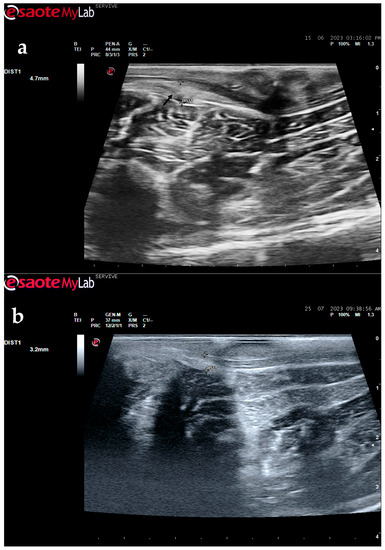

The described technique allows an easy follow-up of the progression of nerve regeneration over time after the induction of a lesion in a controlled surgical environment. For example, after the application of a tube guide, in which the nerve tops of a transected nerve are sutured to the ends of the tube, leaving a gap to be filled inside the biomaterial, immediately after surgery, it is possible to identify the tube guide and the nerve tops inside of it by ultrasound (Figure 9). The tube guide appears as a hyperechogenic structure, at the ends of which the nerve tops are observed (Figure 9a), allowing the measurement of the created gap and its evaluation and measurement over time until the total closure and reconnection of the nerve ends (Figure 9b). In the same way, after the application of end-to-end sutures, in which the ends of the transected nerve are coapted and sutured in order to guarantee their reconnection and anatomical continuity, it is possible to observe the nerve continuity (Figure 10), but at early timepoints after the injury, a small hypoechoic gap appears as a result of the transection. An edema, in association with the inflammatory infiltration resulting from the degenerative phase after the nerve injury, promotes a transient increase in the diameter of the nerve (Figure 10a) that ends up disappearing over time (Figure 10b). In addition to the increase in diameter, due to interstitial edema, the nerve also appears with an increased hyperechogenic appearance. The main advantage of applying ultrasound in the monitoring of nerve regeneration will be to allow the observation of macroscopic morphological changes in the nerve over time, namely changes in its anatomical continuity, in the dimensions of the created nerve gaps, in their diameter, and in the presence or absence of edema and inflammatory infiltrate. Microscopic changes such as endoneurial microvascular degeneration, demyelination/remyelination, and axonal density and reorganization should be later confirmed by more sensitive histomorphometric techniques such as nerve stereology. At the same time, the functional translation of the regenerative process can be evaluated in parallel through functional and behavioral tests, determination of nervous conductivity, and biomechanical and kinematic gait studies.

Figure 9.

Ultrasound image of the left peroneal nerve in a sheep subjected to a transection lesion followed by the application of a tube guide. (a) After 1 week, it is possible to observe the tube guide as a hyperechogenic tubular structure (black arrows) at the ends of which the ends of the transected nerve are inserted (white arrows). DIST1 represents the length of the gap left between the two nerve ends. (b) After 3 months, the tube continues to be perfectly visible (black arrows), and the nerve is introduced into its lumen (white arrows); but now, instead of the gap between the nerve tops, an anatomical continuity of the nerve is observed along the entire tubular lumen (beige arrow), indicating a nerve reconnection. In the center of the tubular lumen, a hypoechoic space not filled by nervous tissue is also observed (brown arrow), indicating that the regenerating nerve has not yet occupied all the available space inside the tube guide. DIST1 represents the nerve diameter, and DIST2 represents the inner diameter of the tube guide.